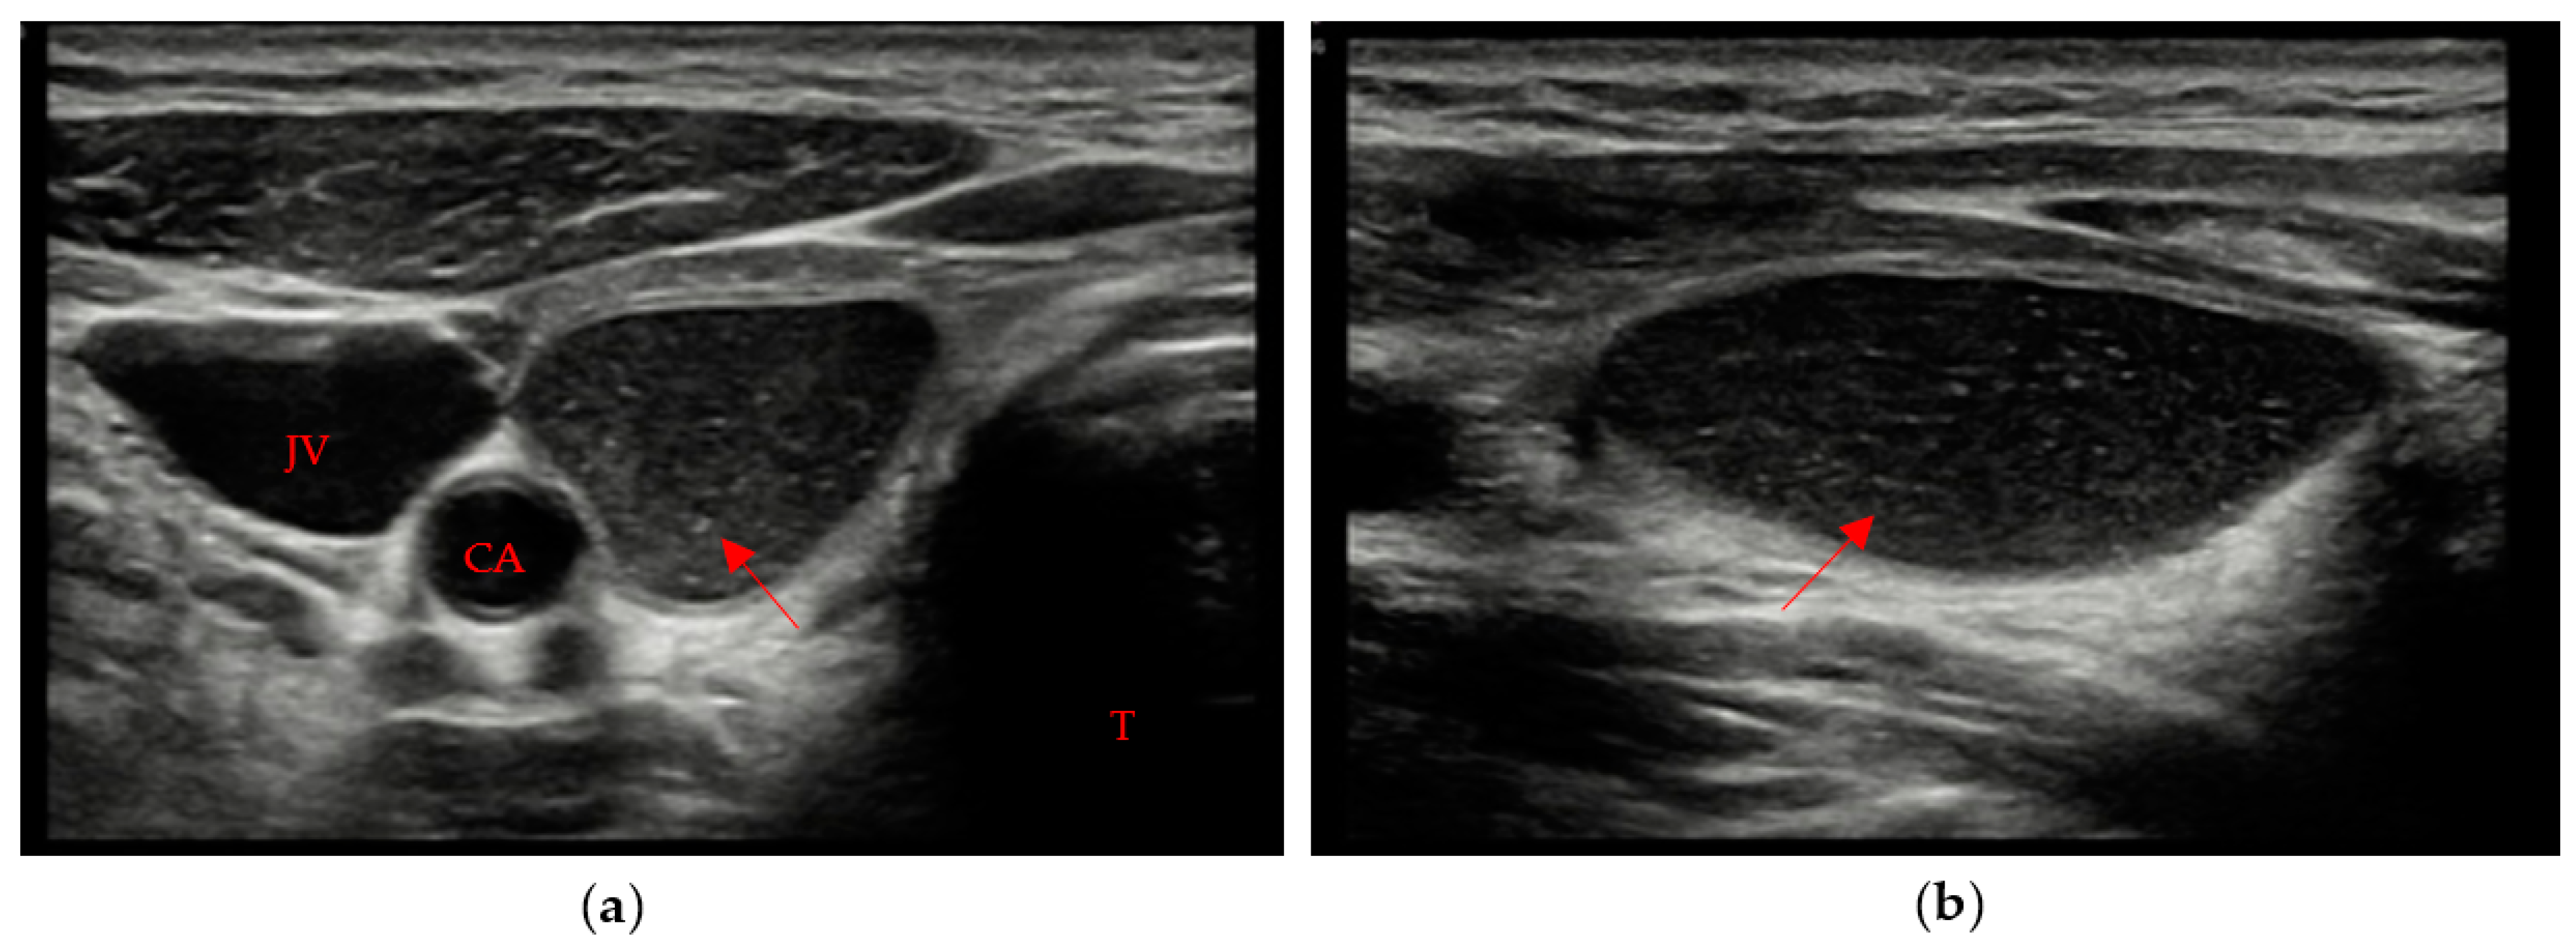

The remaining 3 patients (8% of patients with evidence of residual swab) showed different patterns, with different combinations of margins and ecogenicity. In our experience, we have also found different swab shapes, but the most common are ovoid or pseudo-ovoid shapes; these are the most frequent and most “thyroid-like” shape, and are caused when the remnant has completely obliterated the thyroid space that reproduces the native thyroid gland shape. This form is often associated with the mildly hypoechoic pattern with ill-defined margins (Figure 3a,b).

Figure 3. “Thyroid-like” shape of the swab (red arrow) in a right hemithyroidectomy (the native gland, pointed out by a red star, is still visible on the left). Trachea (T). (a) Axial view; (b) Longitudinal view.